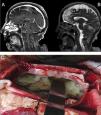

A 72-year-old female patient with history of high blood pressure presented to the emergency with right hemiparesis, aphasia and seizures. Brain computed tomography did not find hemorrhagic lesions and brain magnetic resonance imaging showed no vascular lesions but revealed laminar subdural collection in the right parietal convexity with restriction on the diffusion sequence together with multiple areas of restriction in the subarachnoid space on the bihemispheric convexity (Fig. 1, Panel A and B). It evolved with Glasgow coma scale 8/15, fever and saturation 87% due to aspiration, proceeding to endotracheal intubation. Blood cultures and lumbar puncture were performed. It showed glucose 49mg/dl (serum glucose 484mg/dl), protein level of 946g/dl, leukocytes 3744/mm3 (95% neutrophils), 1.000erythrocytes/mm3. Blood and cerebrospinal fluid cultures revealed the presence of Streptococcus pneumoniae. Neurosurgical intervention was decided with craniectomy and drainage of meningeal empyema (Panel C). The patient completed 8 weeks of ceftriaxone with good clinical outcome.